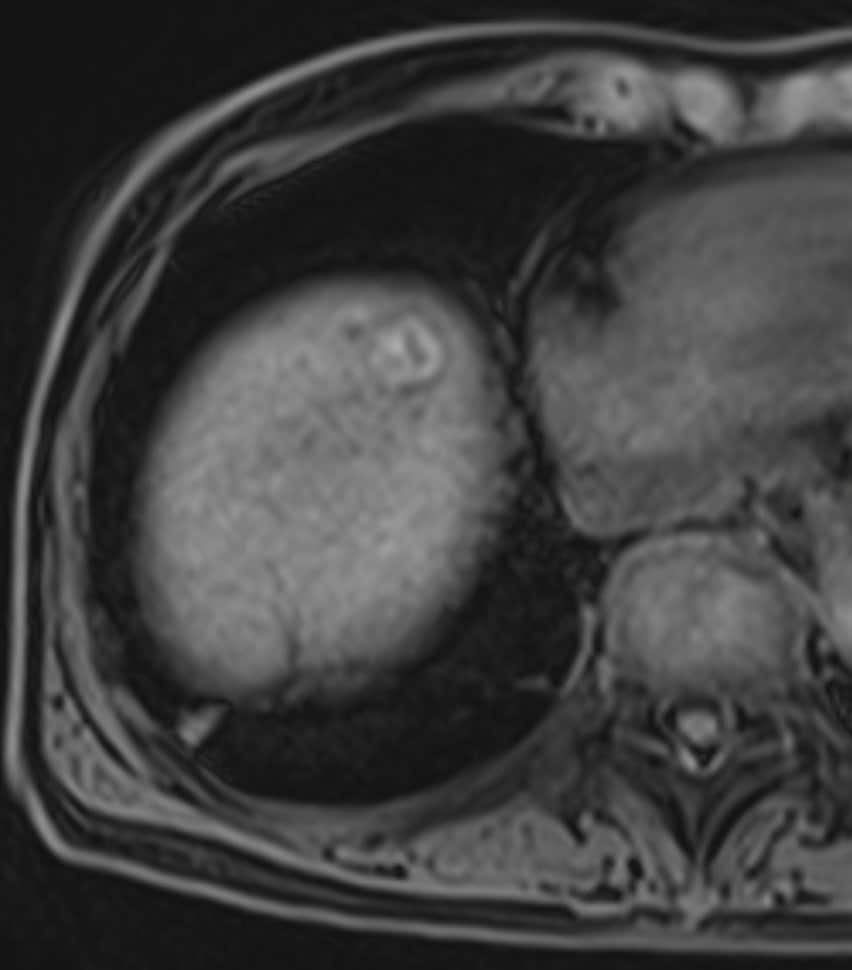

60歳代、女性、53kg、HCC

C型肝炎でフォロー中に肝腫瘍の指摘あり。前医CTにて肝内胆管癌が疑われ、手術目的に当院紹介。肝腫瘍の術前精査目的に再度造影CTとEOB-MRIを施行した。

Necrotic HCCと診断され、切除術を施行された。病理診断でも No residual carcinoma with necrosisとの診断であった。その後再発を認めず、経過観察となっている。

C型肝炎でフォロー中に出現した肝腫瘤について、前医CTではiCCが疑われたが、EOB-MRIにてNecrotic HCCが疑われた。肝切除を施行し、病理学的にもNecrotic HCCが証明された。EOB-MRIは,肝腫瘍の質的診断において有用であることが、あらためて確認された。